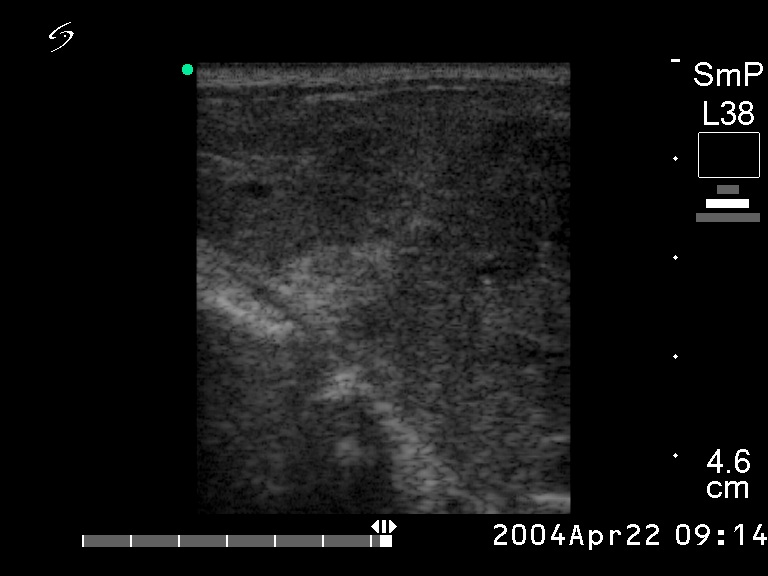

Ultrasonography. A large, hypoechogenic mass occupied almost the entire right lobe. The tumor spread substernal.